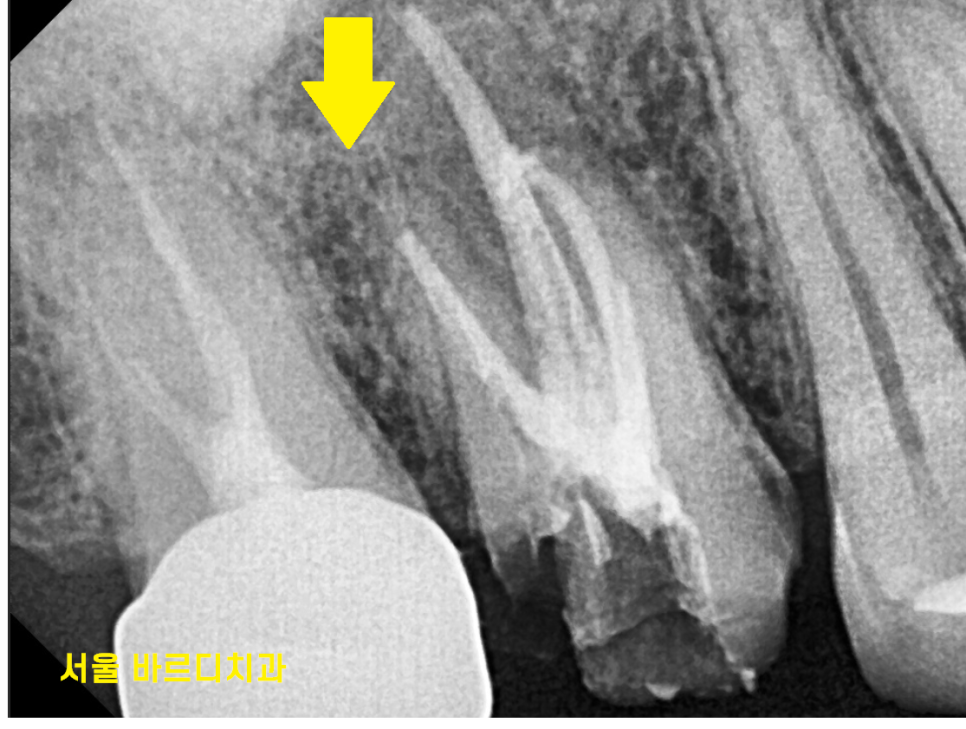

3D ct 등을 통해 정밀한 검사를 진행한 결과,

치아 뿌리 주변의 염증으로 한쪽 뼈를 녹였네요.

ct 상 한쪽 뼈만 녹아있는 상황이라

반대편 뼈에 기대해보면서

뿌리 절반 이상 염증들이

3달의 치료과정을 통해

손톱만큼 줄어들었습니다.

이제 뿌리 끝 까만 부분

거의 보이지 않습니다.

염증이 남아있으면 제대로 뼈가 차지 않는대요.

깨끗하게 염증이 없어졌기 때문에

까맣게 녹아 버린 뼈가

다시 하얗게 채워진 모습을 볼 수있네요~